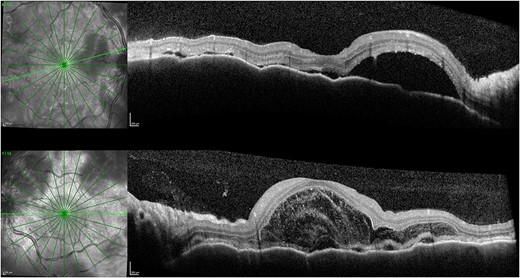

One week after initial review, the patient presented with eye casualty with deteriorated vision of 6/9 in the right eye and count fingers in the left eye. Intraocular pressure was within normal limits in both eyes. Anterior segment examination showed mild anterior uveitis with mild conjunctival injection, 1+ cells in the right eye, 2+ cells in the left eye, and 0.5+ cells in the anterior vitreous of both eyes. No keratic precipitants or posterior synechiae were present in either eye. Fundoscopy revealed bilateral hyperemic discs and 360° choroidal detachments with serous retinal detachment involving the maculae (Fig. 1). There was no evidence of vitritis or retinitis. OCT illustrated detachments of the neurosensory retina and bacillary layers (Fig. 2). Fundus fluorescein angiogram (FFA) demonstrated bilateral disk hyperfluorecence, macular hyperfluorescent pinpoints, and no evidence of retinal vasculitis or ischemia (Fig. 3).

FFA demonstrating right (A) and left (B) disc hyperfluorecence and macular hyperfluorescent pinpoints, and pooling in areas corresponding to serous detachments.